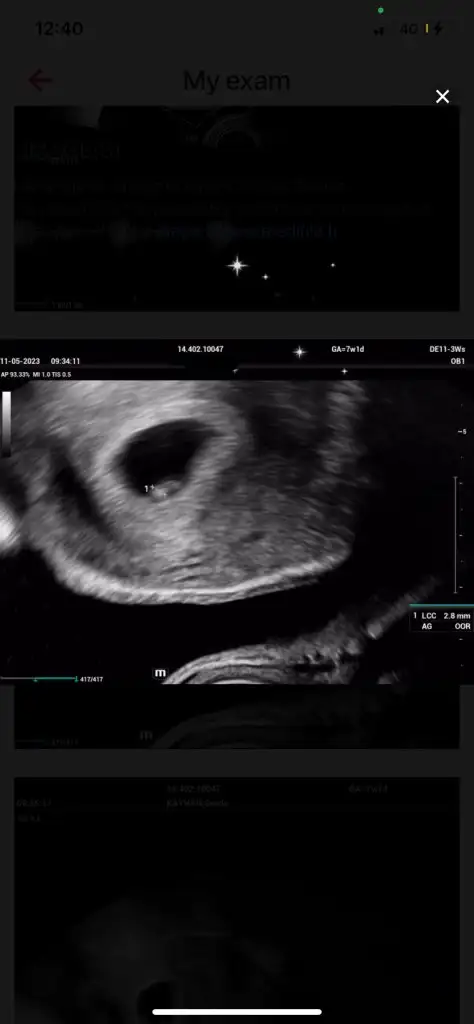

Bugün bebeği ve kalp atışını gördük çok şükürBen direk alttan muayene etmesini istedim çünkü karından çok küçük olduğu için görünmüyorlar genelde aslında aletlerle de alakalı iyi bir aletse bence karından da rahat görünüyor iyi hastanelerin. Evet benim de bildiğim kadarıyla o yuvarlak siyah halkın etrafındaki beyaz Çember yok kesesi deniliyor muş ben de çok bilmiyorum benim de bundan önce bir kimyasal bir normal kaybım olmuştu. O yüzden biraz tedirginim ama inşallah güzel sonuçlar alacağız güzel düşünmek lazım sizinde güzel haberleriniz olur mutlaka buradan haberleşelim

canım ben de gittim bugun bebeği de gördüm kalbini de dinledim 7+6ydım doktor 7haftalık geç döllenmedir sorun yok dedi gayet iyi kalbi kese falan dedi karından göründü zaten cok sükür insallah hepimiz de sağlıklıca kucagımıza alırızHadi diğerinin de kalp atışını görürsün inşallahbenim de kan pıhtılaşmam varmış. 3-4 gün önce geldi sonucum. Aspirin başlayacağım bu akşam. Karından görünebiliyorsa sizin süper. Çünkü benim karından baktı. Bsey göremiyorum. Çok kötü. Üzgünüm falan dedi. Çok kötü oldum ben de. Sonra vajinalden bakınca gördü çok şükür